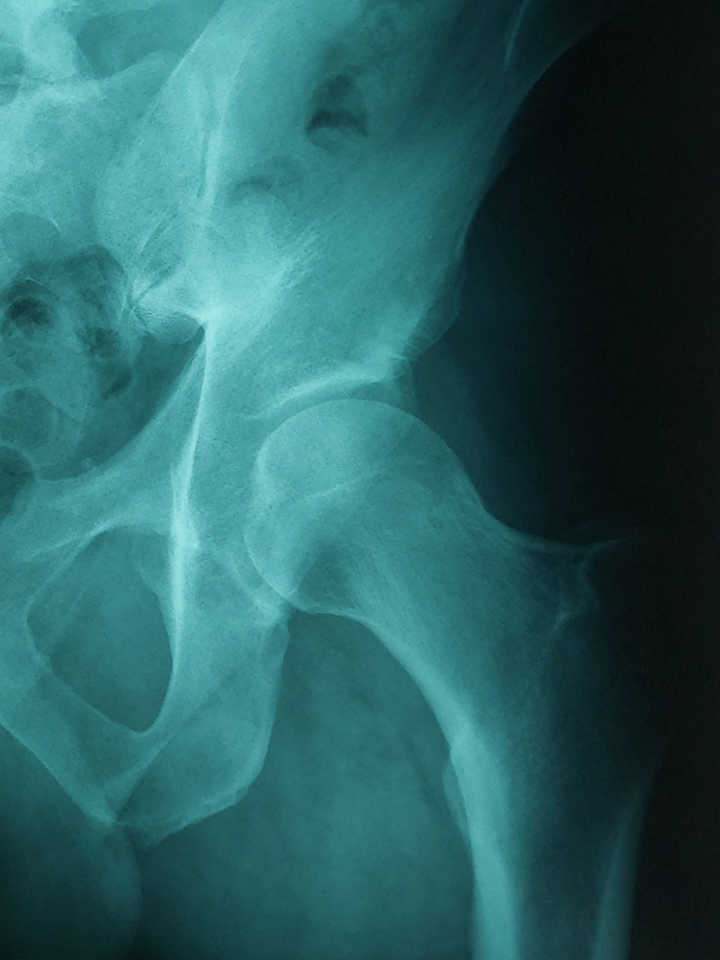

Αρθροσκόπηση ισχίου στη δυσπλασία: Παρόμοια αποτελέσματα και επιβίωση της άρθρωσης σε σύγκριση με μη δυσπλαστικά ισχία, 10 χρόνια μετά

Η δυσπλασία του ισχίου θεωρείται από μερικούς αντένδειξη για αρθροσκόπηση ισχίου. Σε γενικές γραμμές η επιστημονική κοινότητα αντιμετωπίζει τη δυσπλασία του ισχίου με μεγαλύτερη ματαιοδοξία στοχεύοντας σε μία αρθροπλαστική ισχίου μακροπρόθεσμα. Ωστόσο νέα μελέτη έδειξε παρόμοια αποτελέσματα της αρθροσκόπησης ισχίου, όταν συγκρίθηκαν ομάδες ασθενών με δυσπλαστικό και μη δυσπλαστικό ισχίο.

Ο σκοπός της μελέτης ήταν η αξιολόγηση των μακροπρόθεσμων αποτελεσμάτων της αρθροσκόπησης ισχίου επί μηροκοτυλιαίας πρόσκρουσης σε ασθενείς με δυσπλασία του ισχίου και η σύγκριση με μία ομάδα ελέγχου.